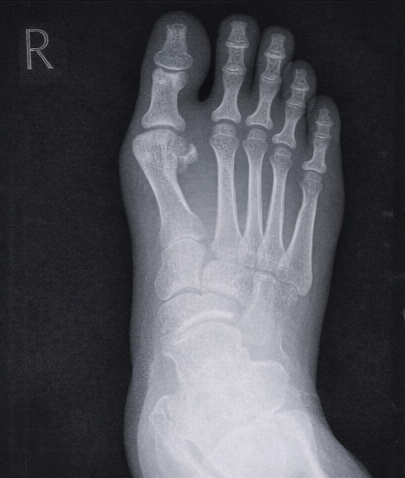

Plain radiography of the foot showed soft tissue swelling without evidence of osteomyelitis.